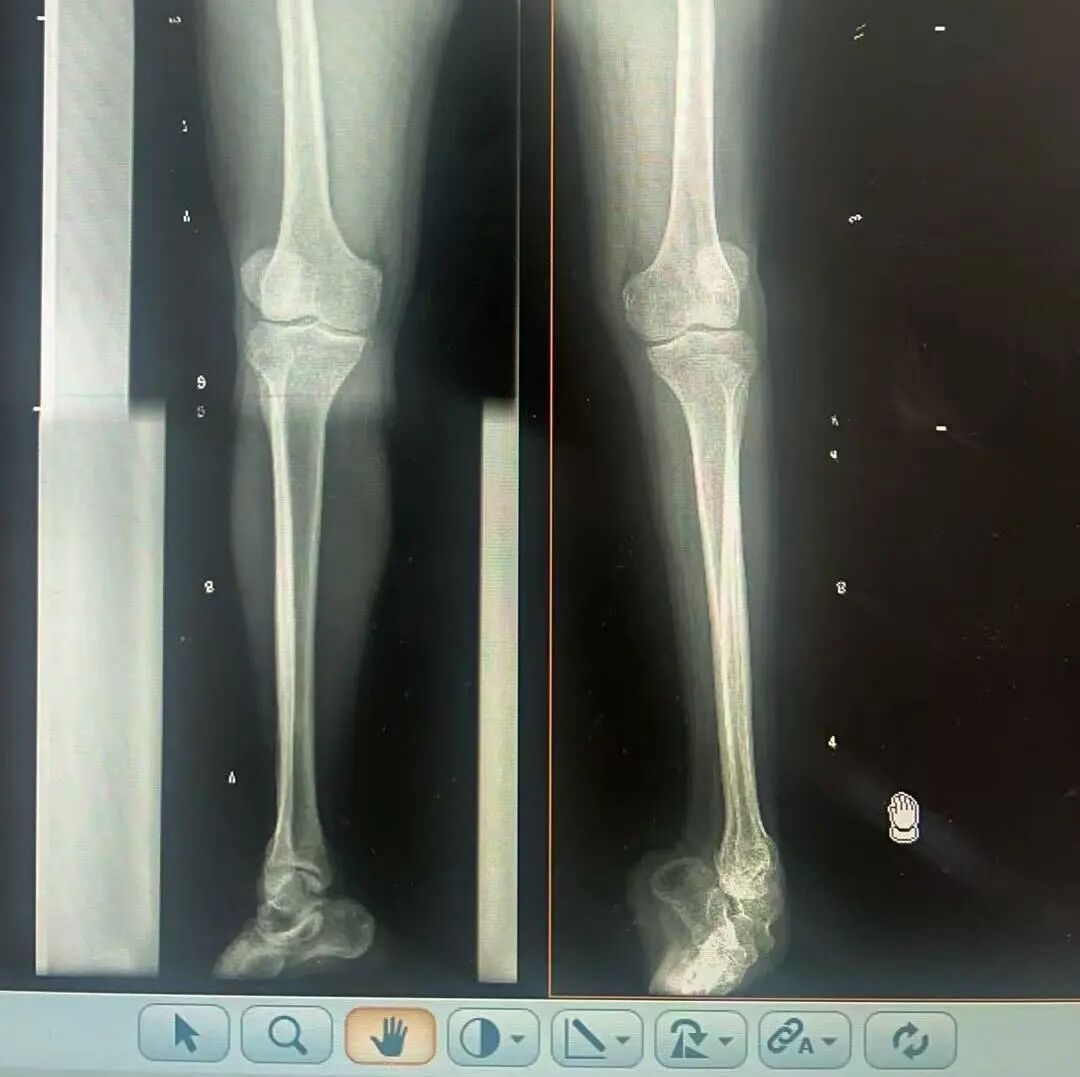

術(shù)前X光片 VS 術(shù)后治療效果

骨科隨即為陽(yáng)先生進(jìn)行了全面的檢查。診斷明確而復(fù)雜:陽(yáng)先生患有脊髓灰質(zhì)炎后遺癥、左踝馬蹄內(nèi)翻足、骨盆傾斜……面對(duì)這張沉甸甸的診斷書,由肢體功能重建顯微修復(fù)學(xué)科組長(zhǎng)鄭群龍所帶領(lǐng)的醫(yī)療團(tuán)隊(duì)沒有畏懼,“這是一個(gè)家庭38年的堅(jiān)守與期盼,我們必須全力以赴”

針對(duì)陽(yáng)先生的復(fù)雜情況,鄭群龍醫(yī)師團(tuán)隊(duì)制定了詳盡的手術(shù)方案:左踝關(guān)節(jié)融合+馬蹄足畸形矯正+跟腱延長(zhǎng)+外固定架固定術(shù)。手術(shù)的核心,正是伊里扎洛夫技術(shù)。這項(xiàng)技術(shù)如同精密的“時(shí)空建筑學(xué)”,通過微創(chuàng)安裝環(huán)形外固定架,前足-后足安裝鋼環(huán),再將足的鋼環(huán)與脛骨的固定鋼環(huán)在踝關(guān)節(jié)前、后、左、右用帶關(guān)節(jié)的螺紋桿連接,由此構(gòu)建成一個(gè)能體外牽拉調(diào)控的三維立體構(gòu)型,在術(shù)后進(jìn)行精準(zhǔn)、緩慢的調(diào)整,一寸一寸逐步將畸形的骨骼、軟組織恢復(fù)到正常位置。

9月1日,在全麻狀態(tài)下,陽(yáng)先生接受了伊里扎洛夫外固定架安裝術(shù)。鄭群龍團(tuán)隊(duì)在陽(yáng)先生左足足踝部植入克氏針及半針,安裝外固定架,通過支架的機(jī)械結(jié)構(gòu)對(duì)馬蹄內(nèi)翻畸形進(jìn)行緩慢、持續(xù)的牽拉矯正。術(shù)后,鄭群龍團(tuán)隊(duì)反復(fù)指導(dǎo)訓(xùn)練陽(yáng)先生父子進(jìn)行外固定架的日常調(diào)試,按照預(yù)定計(jì)劃每日調(diào)整螺桿,逐漸糾正足部畸形,并配合專業(yè)的康復(fù)訓(xùn)練,包括踝關(guān)節(jié)主動(dòng)及被動(dòng)活動(dòng)、下肢肌力訓(xùn)練等項(xiàng)目促進(jìn)陽(yáng)先生腿部肢體功能恢復(fù),預(yù)防肌肉萎縮及關(guān)節(jié)僵硬。